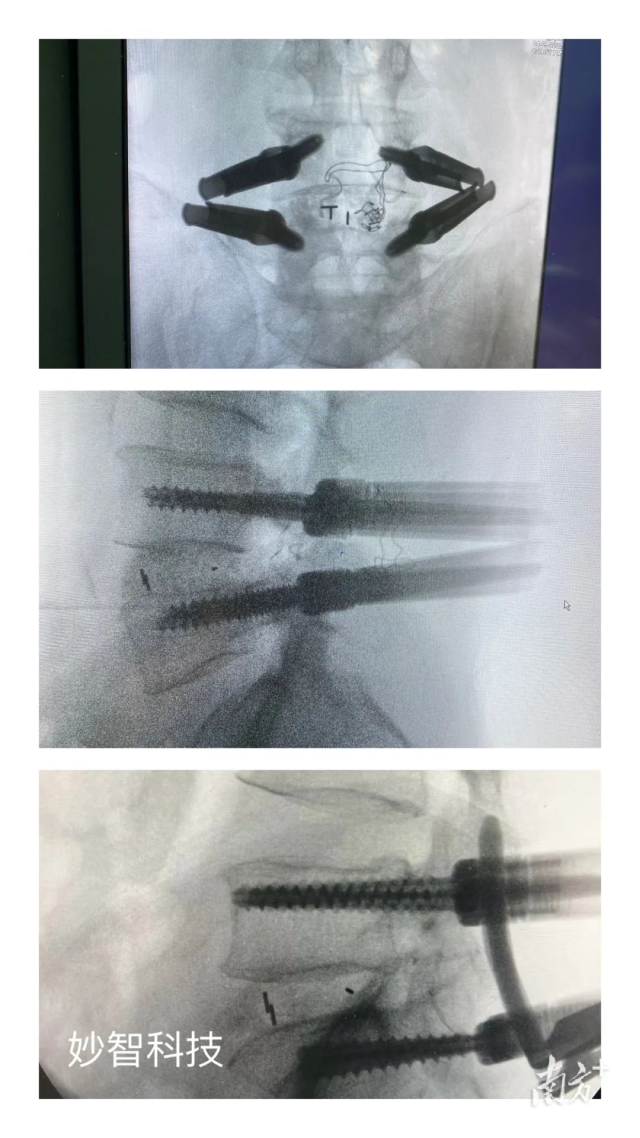

妙智科技研發(fā)的骨科機器人在臨床中試驗

由於新型醫療器械壹般研究周期較長(cháng),目前,妙智科技研發(fā)的骨科機器人仍在臨床試驗階段。截至2022年底,妙智科技已經(jīng)完成了近50例臨床病例,預計今年計劃將完成取證並開(kāi)始售賣(mài)。